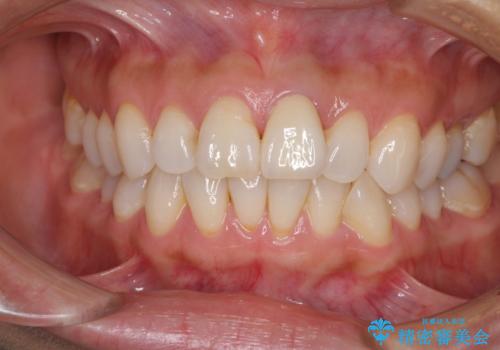

変色とともに、捻れていたことも気になっていたので、その両方を解決させることとしました。

オーダーメイドタイプのクラウンを選択いただいたので、まるで天然の歯と見間違うほど自然に仕上がり、患者様には大変満足していただきました。